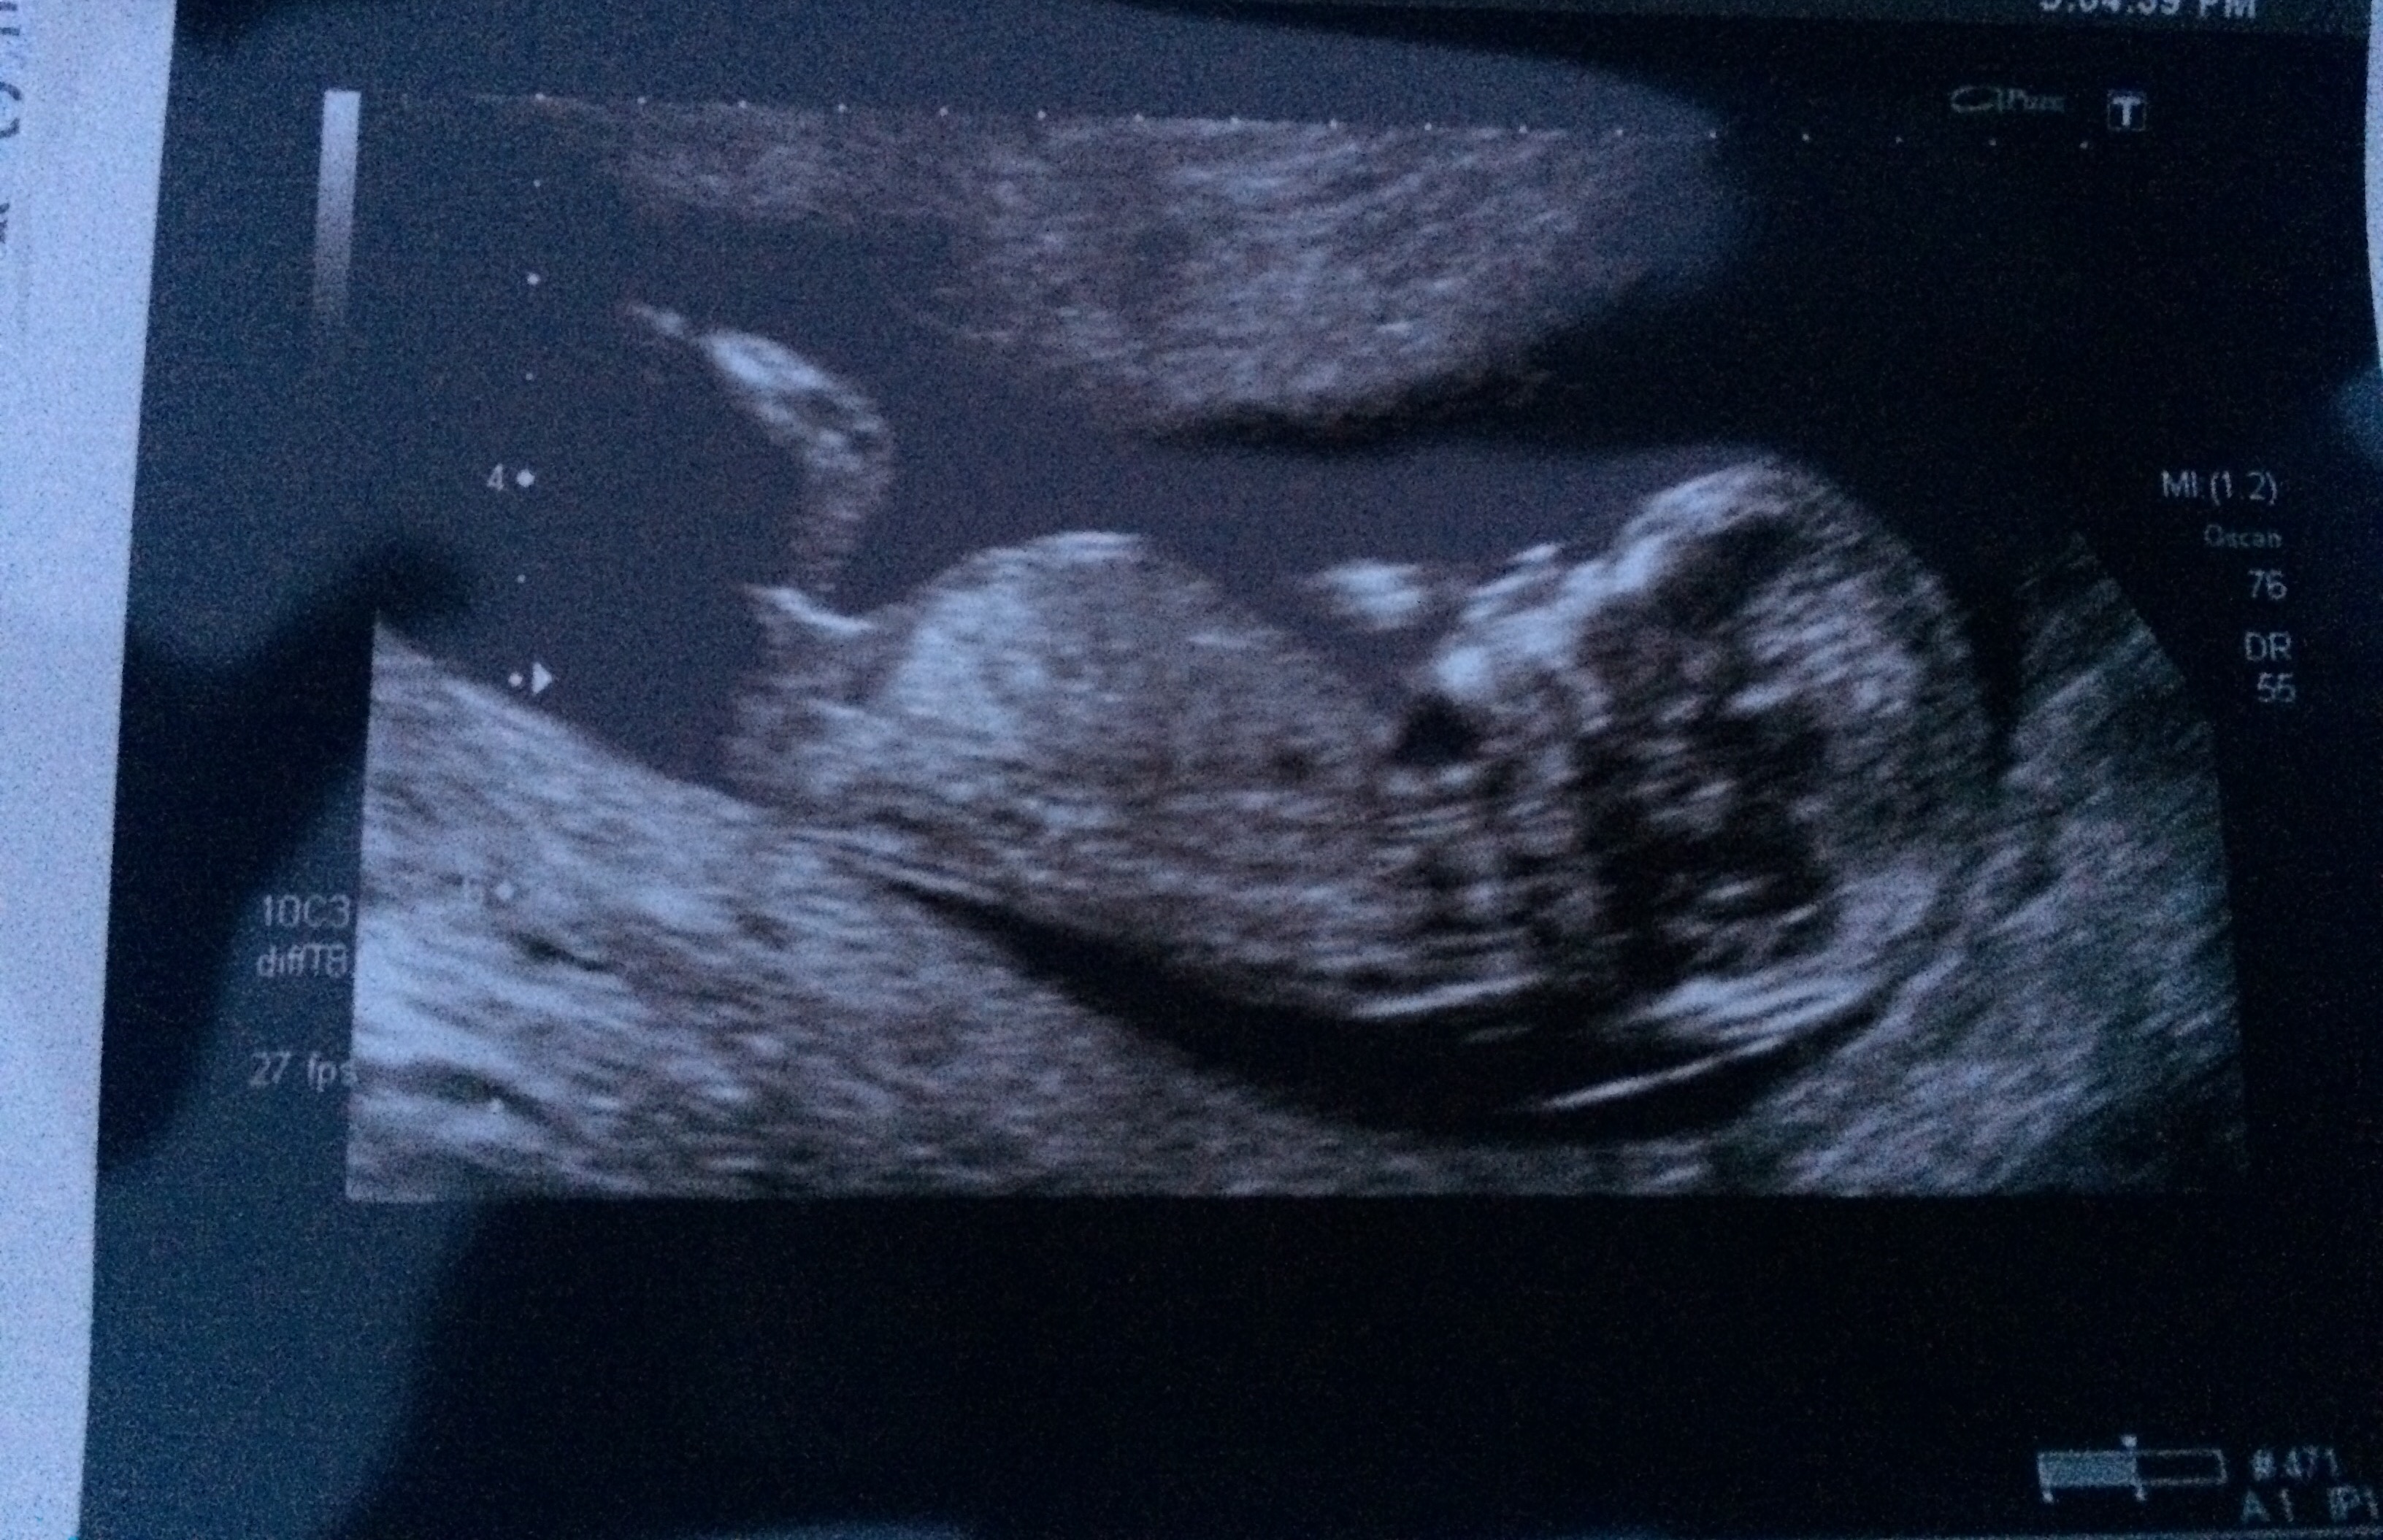

Any gender guesses for my 12+5 scan please?

The baby looks slightly angled in the bottom photos. Accounting for that I would say girl.

the nub has risen .so more boyish.

I think girl based on nub